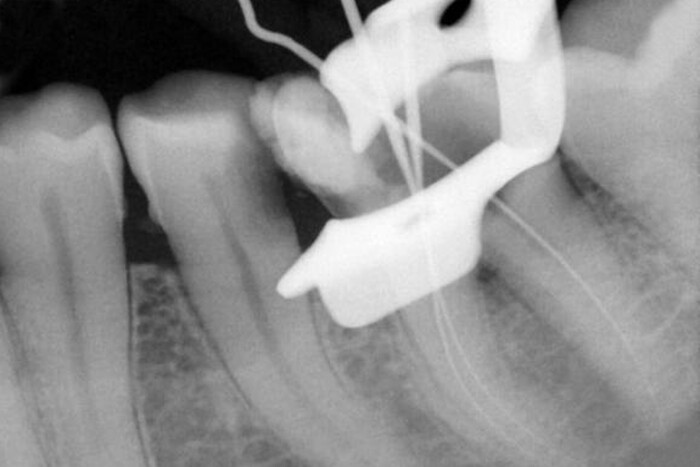

Закрытие перфорационного дефекта цементом на основе кальций-силиката с использованием внутренней матрицы: Отчет о случае

В данном отчете описан нехирургический эндодонтический метод лечения дистолингвальной перфорации дна первого моляра нижней челюсти с использованием внутренней матрицы и минерального триоксидного агрегата (МТА). Пульпарная камера была надлежащим образом очищена, и после установки синтетического колла...